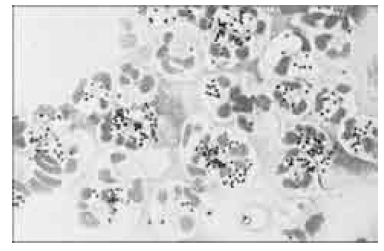

Com base na figura acima, que mostra microrganismos juntamente com células humanas, julgue os itens a seguir, acerca dos diversos testes utilizados em microbiologia.

Para a pesquisa de microrganismos pelo método de Gram no líquido sinovial de aspecto límpido, pode-se centrifugar a amostra na tentativa de concentrar os agentes infecciosos presentes.

Staphylococcus aureus são cocos esféricos catalase positivos que costumam se apresentar em grupos, de forma semelhante aos mostrados juntamente com neutrófilos na figura.

A coloração de Gram é o método adequado para diferenciar cocos de bacilos, que são corados com cores diferentes.